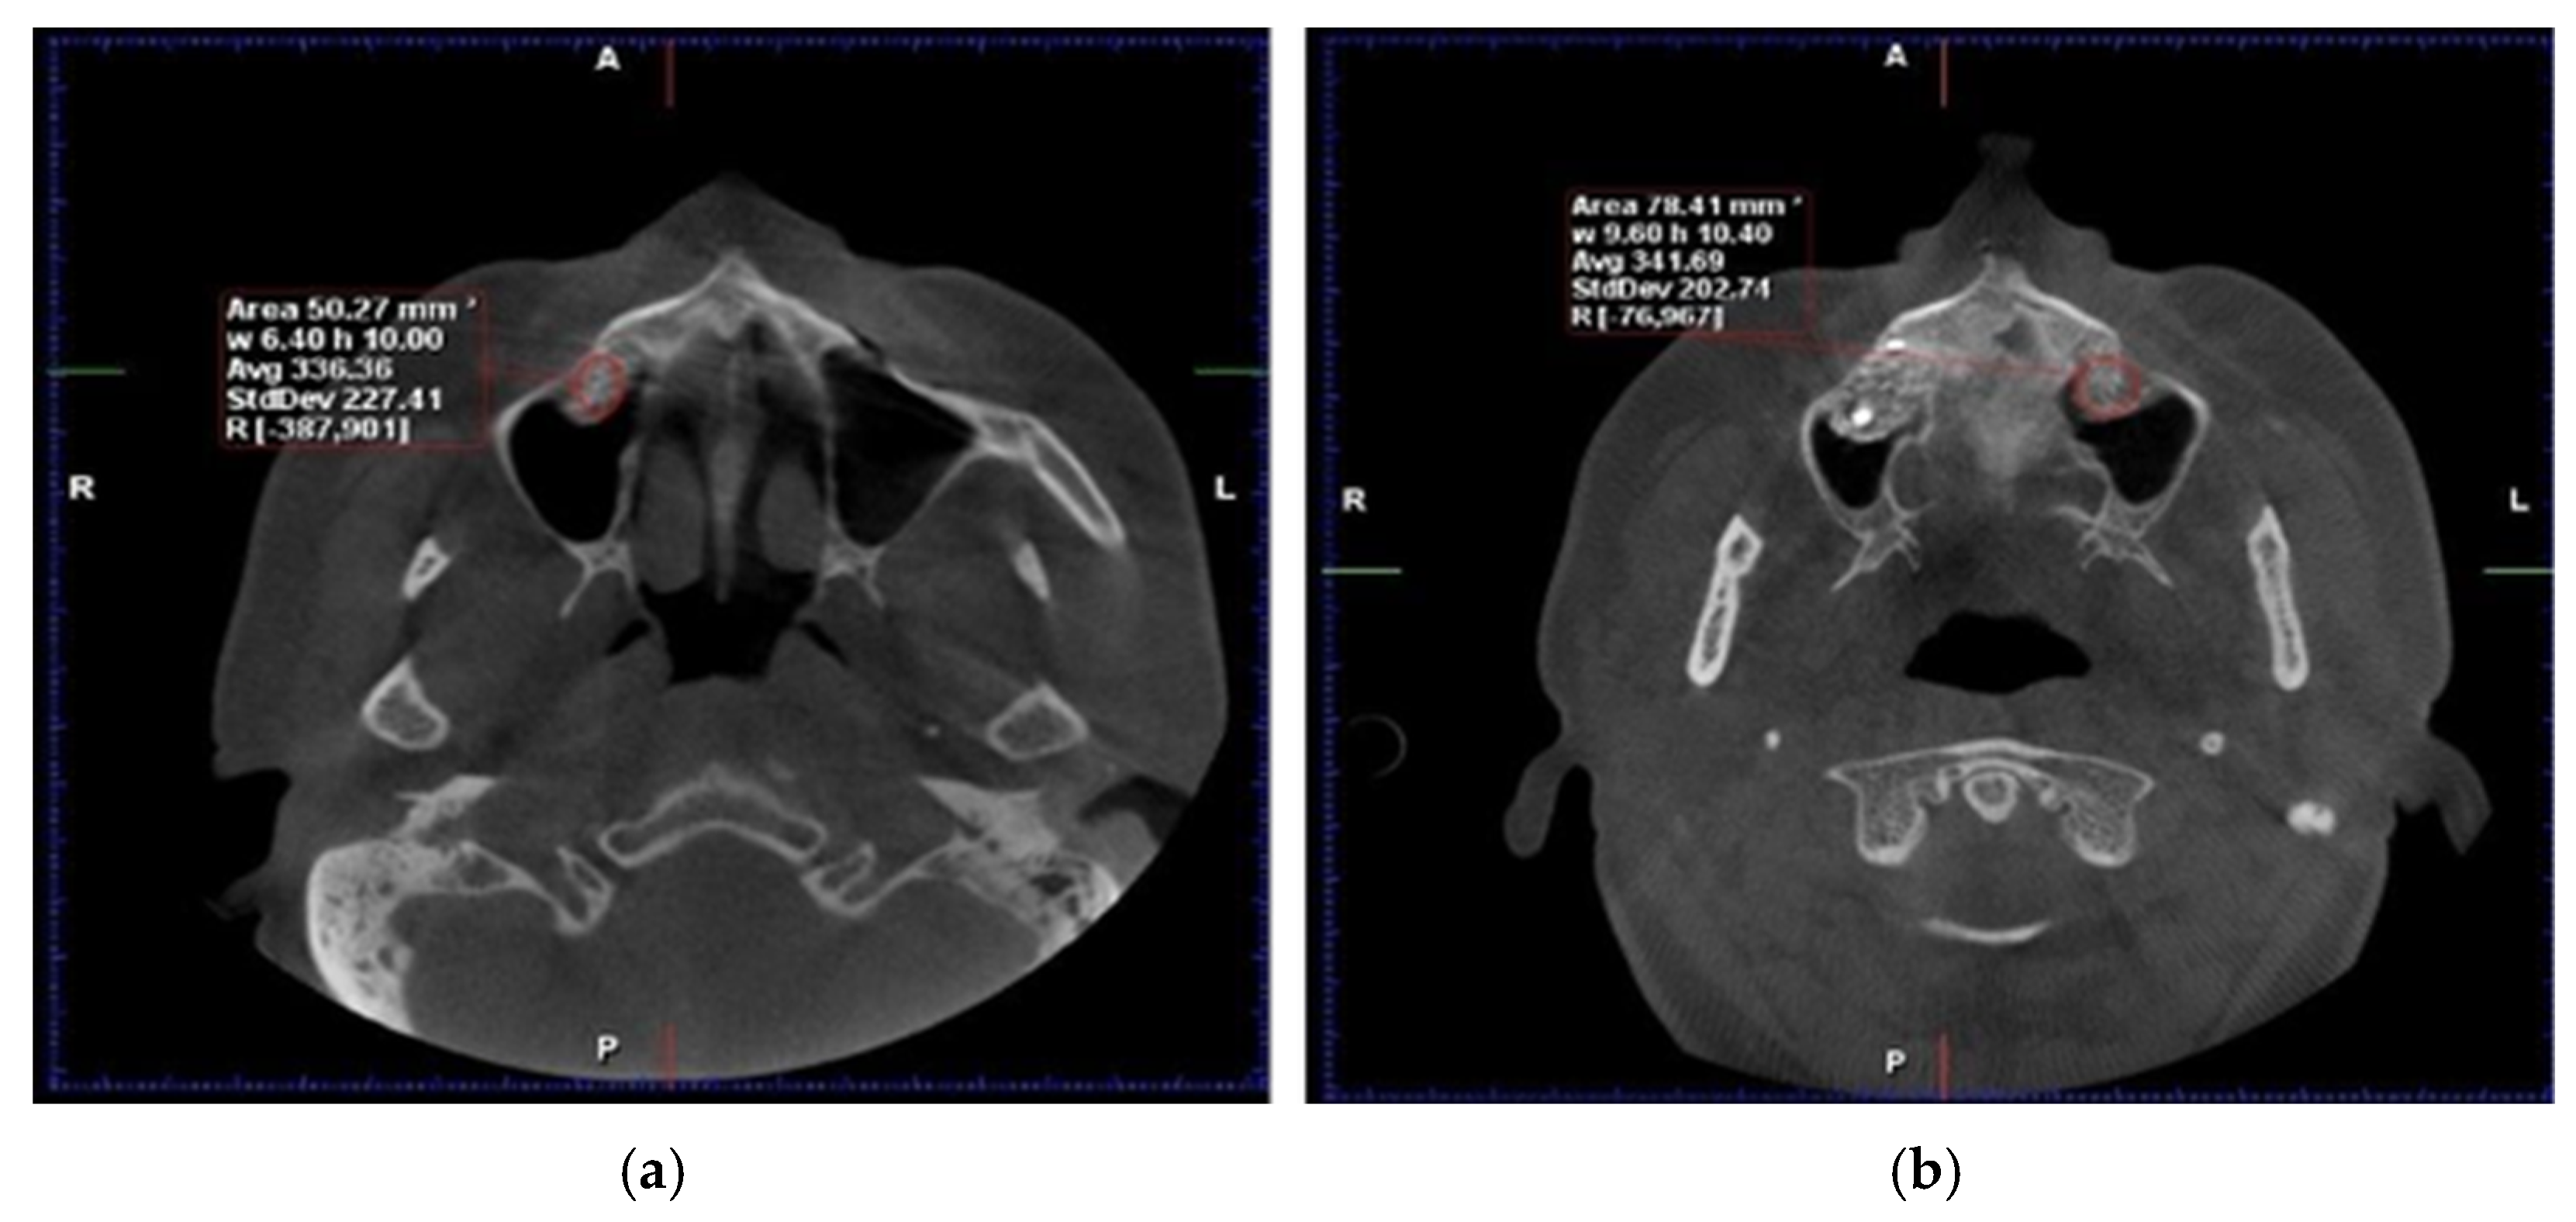

Cone-beam computed tomography (CBCT) and dual-energy X-ray absorptiometry (DEXA) scans were obtained preoperatively, immediately postoperatively, and at 6 months to assess bone volume and density. After six months of healing, bone core biopsies were collected during implant site preparation, and dental implants (Tag Medical Ltd., Kibbutz Ga’aton, Israel) were placed. A follow-up evaluation was performed 10 years after implant placement to assess long-term outcomes, including implant survival and patient-reported satisfaction. The primary analysis in this study was based on imaging and biopsy results collected within the first six months. (Figure 1). However, the 10-year follow-up data focused on long-term implant success and patient-reported outcomes rather than additional CBCT or biopsy examinations (Figure 2).

3.2. Bone Density

At six months postoperatively, CBCT analysis revealed higher mean bone density in SrR-treated sites compared with untreated controls. Over the 10-year follow-up period, SrR-treated quadrants demonstrated a mean increase of 22.94% in bone density, whereas control quadrants showed a 12.51% increase.

The Hounsfield Unit (HU) values remained consistently higher in SrR sites throughout the follow-up period, confirming a sustained enhancement in mineralization (Table 2).

Figure 1. Axial CBCT reconstructions. Evaluation of HU density six months post−intervention: (a) with RS administration, (b) without adjuvant therapy involving RS (Personal Collection).